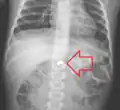

AP X ray showing a 9mm battery in the intestines -

Lateral X ray showing a 9mm battery in the intestines -